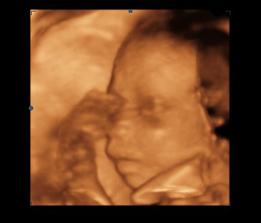

14.1.2010 3D ultrazvuk podľa PM presne 13tt+0 , na drobčeka sa bol pozrieť 1.krat aj tatinko, bolo to krásne 🙂 /////